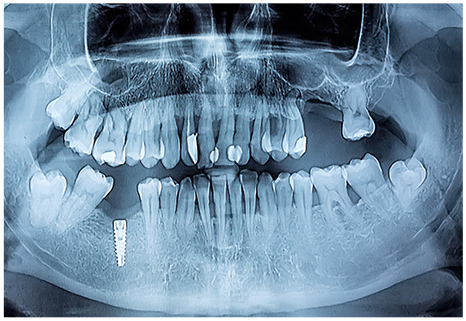

バイトウイングとは歯と歯の間のむし歯を診断するレントゲン撮影の方法です。

歯と歯の間は目で見ただけでは分からないので、バイトウイングでしっかり検査します。

レントゲン写真を撮影しお口全体の状態を把握したうえで全体的な治療計画を立てます。